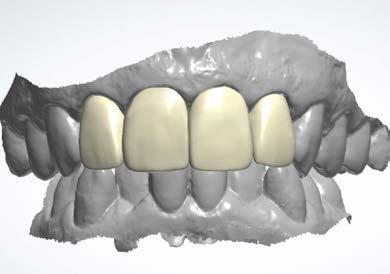

Se presenta una paciente clase ll esquelética en los estudios extrao rales en la fotografía de frente se ve hiperdivergente con una mordi da profunda de 5mm, un diastema, y refiere como motivo de consulta "no me gusta el espacio entre mis dien tes" (Figura 1).

En los estudios intraorales de inicio en las fotografías se muestra en la de frente el diastema anterior, con la línea media dental superior e inferior no coincidentes, la mordida profun da anterior (Figura 2), en la lateral derecha clase l molar y canina bila teral (Figura 3), el apiñamiento leve superior e inferior y la forma de las arcadas.

La duración del tratamiento fue de 1 año 9 meses, manteniendo el perfil facial estético y funcional (Figura 9).

Estudios intraorales finales

En las fotografías intraorales finales se ve la corrección del apiñamiento maxilar y mandibular, la forma de las arcadas es ovalada, se consiguió guía de desoclusión canina derecha e izquierda, la mordida profunda

anterior (Figura 10), la estabilidad oclusal, la máxima intercuspidación, el paralelismo radicular y oclusión funcional, el cierre de diastema ante rior, las líneas medias superior-infe rior coincidieron ambas con la facial.

Figura 1. Extraoral de inicio de frente. Figura 2. Intraoral de frente derecha, izquierda. Figura 3. Oclusal superior e inferior arcadas cuadrada. Figura 4. Radiografía lateral de cráneo. Figura 5. Rx Panorámica.

Manejo de maloclusión de mordida profunda y diastema anterior Figura 6. Intraoral de frente, derecha, izquierda. Figura 7. Intraoral de frente, derecha, izquierda.

Figura 8. Vista oclusal forma de las arcadas oval con termo formador superior e inferior. Figura 9. Extraoral de frente, final. Figura 10. Comparación frente inicio, vista oclusal superior e inferior, en oclusión lado derecho izquierdo final.